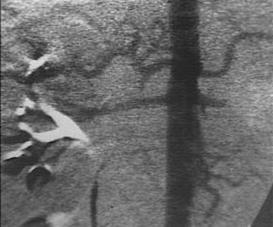

Lipsa vascularizatiei rinichiului stang Angiograma

Lipsa vascularizatiei rinichiului stang

Leziune renala prin impuscar Explozie de rinichi Angiograma